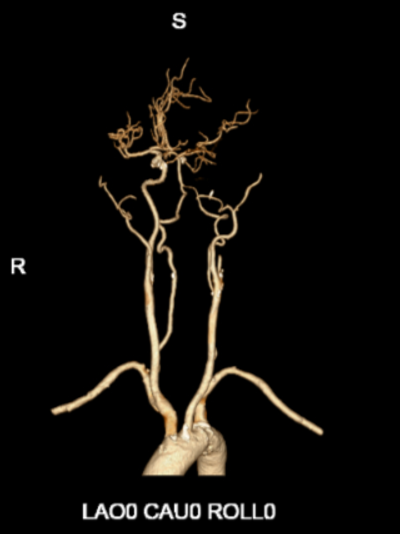

右侧颈内动脉造影动脉末期可见左侧大脑前动脉经软膜支向左侧大脑中动脉供血区域代偿,后循环未向左侧大脑中动脉代偿。

左侧颈总动脉造影可见颈内动脉闭塞,动脉末期可见颈外动脉经眼动脉向颈内动脉代偿,颈内动脉末端以远不显影。

在泥鳅导丝及5F MPA1造影管配合下将6F股动脉长鞘至于左侧颈总动脉行路图,在200cm Sur-reach®微导丝配合下将2.5*15mm颅内球囊扩张导管扩张后,将6F导管鞘通过颈内动脉起始部闭塞段,行路图可见颈内动脉颈段至海绵窦段后膝处血栓影,左侧大脑中动脉闭塞。